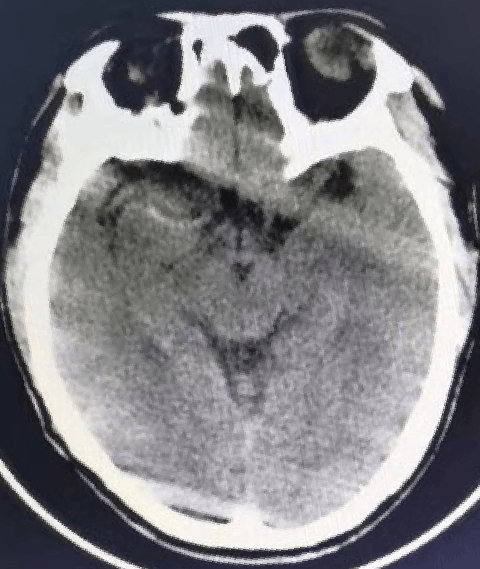

术前诊断:

头颅CT提示:右侧大脑中动脉高密度征,ASPECTS 7分。

CTA:右侧大脑中M1闭塞。

CTP:右侧大脑半球广泛缺血,梗死体积22ml,半暗带体积130ml